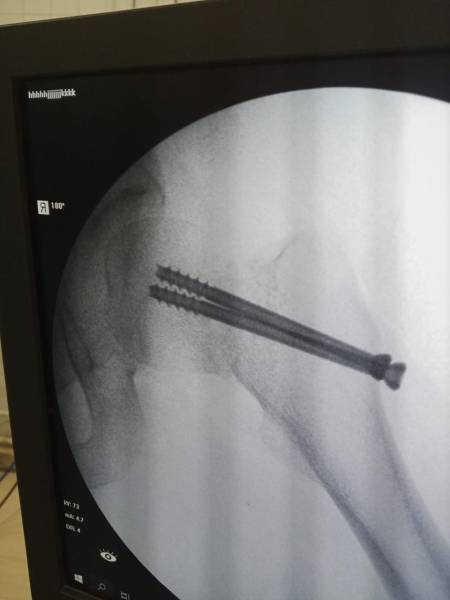

- إجراء عمليات جراحية معقدة و دقيقة في مجال العظام و المفاصل و الكسور و الإصابات ، رغم الضغط الكبير على المستشفى و أعداد المراجعين الكبيرة.

- تطبيق تقنيات جراحية حديثة و متقدمة، و ذلك في ظل التحديات التي يواجهها الفريق بسبب أعداد المرضى و المراجعين الكبيرة.